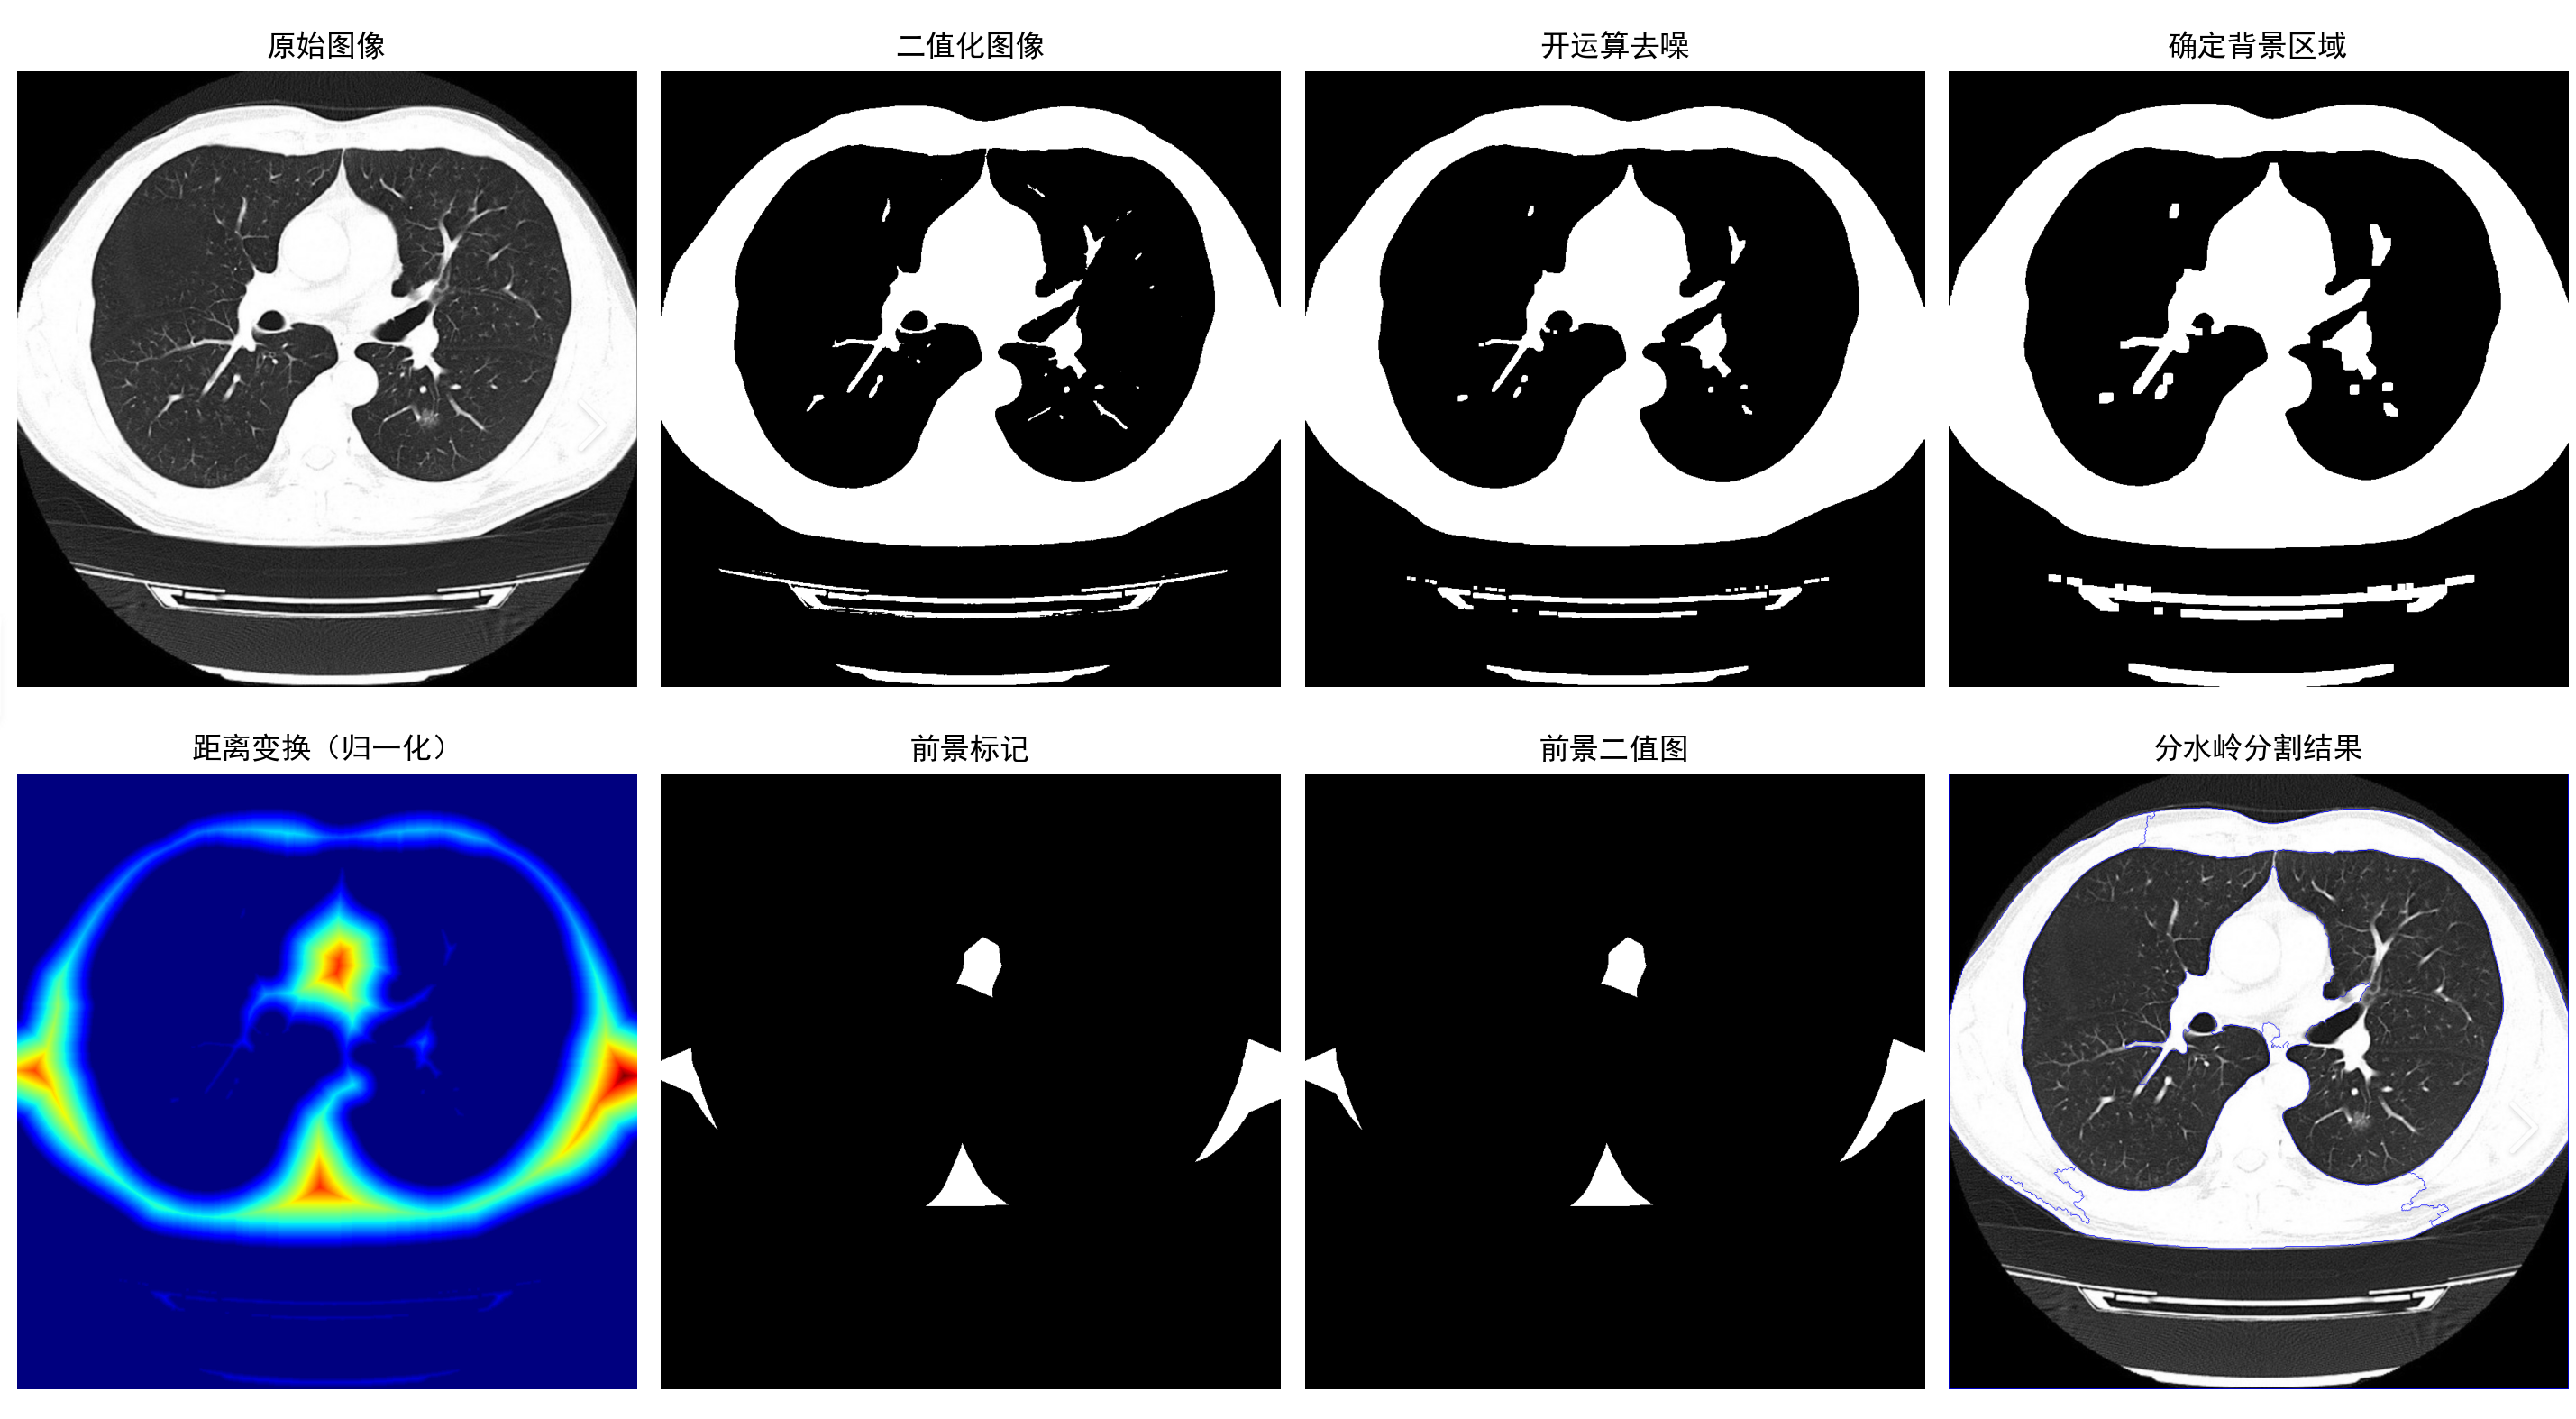

3.分水岭实现医学诊断

分水岭算法的主要目标在于找到图像的连通区域并进行分割。在实际处理过程中,如果直接以梯度图像作为输入,则容易受到噪声的干扰,产生多个分割区域;如果对原始图像进行平滑滤波处理后再进行梯度计算,则容易将某些原本独立的相邻区域合成一个区域。当然,这里的区域主要还是指图像内容变化不大或灰度值相近的连通区域。

利用分水岭对肺癌细胞进行分割诊断处理的Python代码:

import cv2 as cv

if __name__ == "__main__":# 1. 读取图像img_path = "37.jpg"img = cv.imread(img_path)# 2. 执行分水岭分割,获取所有显示结果display_results = watershed_demo(img)# 3. matplotlib 子图布局(2行4列,容纳8个结果图)plt.figure(figsize=(16, 8))  # 窗口大小:宽16英寸,高8英寸plt.rcParams['font.sans-serif'] = ['SimHei']  # 显示中文标题plt.rcParams['axes.unicode_minus'] = False  # 解决负号显示异常# 4. 逐个绘制子图for idx, (title, img_data) in enumerate(display_results, 1):plt.subplot(2, 4, idx)  # 2行4列,第idx个子图if len(img_data.shape) == 3:  # 彩色图像(RGB格式)plt.imshow(img_data)else:  # 灰度图像(二值图/距离变换图等)# 距离变换图用jet色表更直观,其他灰度图用gray色表cmap = 'jet' if "距离变换" in title else 'gray'plt.imshow(img_data, cmap=cmap)plt.title(title, fontsize=12)  # 添加子图标题plt.axis('off')  # 关闭坐标轴,聚焦图像# 5. 调整子图间距,避免标题/图像重叠plt.tight_layout()# 6. 显示所有子图(阻塞窗口,按关闭键退出)plt.show()

实验表明,采用标记分水岭算法对肺部图像进行分割具有良好的效果,能在一定程度上突出病变区域,起到辅助医学诊断的目的,具有一定的使用价值。